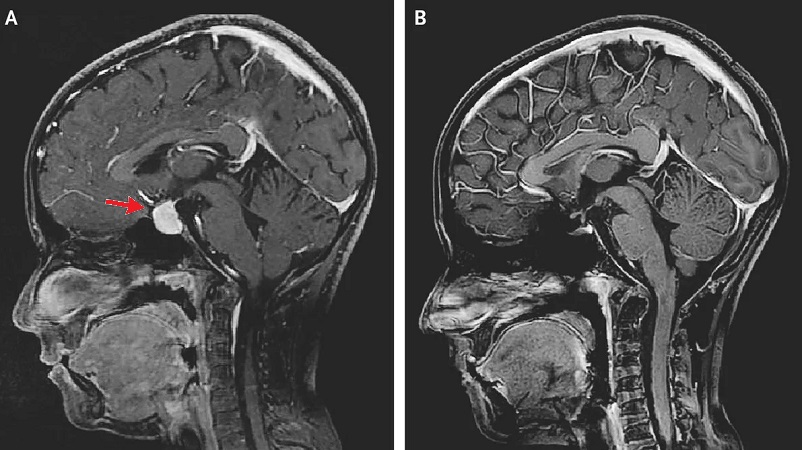

1. Отбор и обследование. На этом этапе проводится комплексная оценка состояния пациента, включая МРТ головного мозга, нейропсихологическое тестирование и так называемый «леводопа-тест» для оценки реакции на препарат.

2. Предоперационная подготовка. Включает в себя планирование операции на основе данных МРТ, консультации с анестезиологом и другими специалистами. Накануне операции на голову пациента устанавливается специальная стереотаксическая рама для обеспечения высочайшей точности введения электродов.